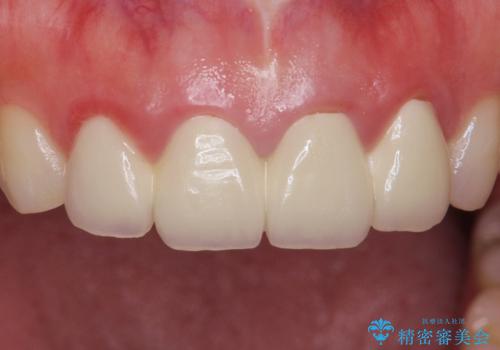

自然な仕上がりに大変喜んで頂けました。

単冠かつ適合の良いクラウンにより清掃性が良くなり、歯茎の腫れ・出血もなくなりました。

天然歯と見紛うほど自然なセラミッククラウンは、熟練した技工士さんの技術の賜物です。

クラウンの種類:ジルコニアオールセラミッククラウン エクセレント